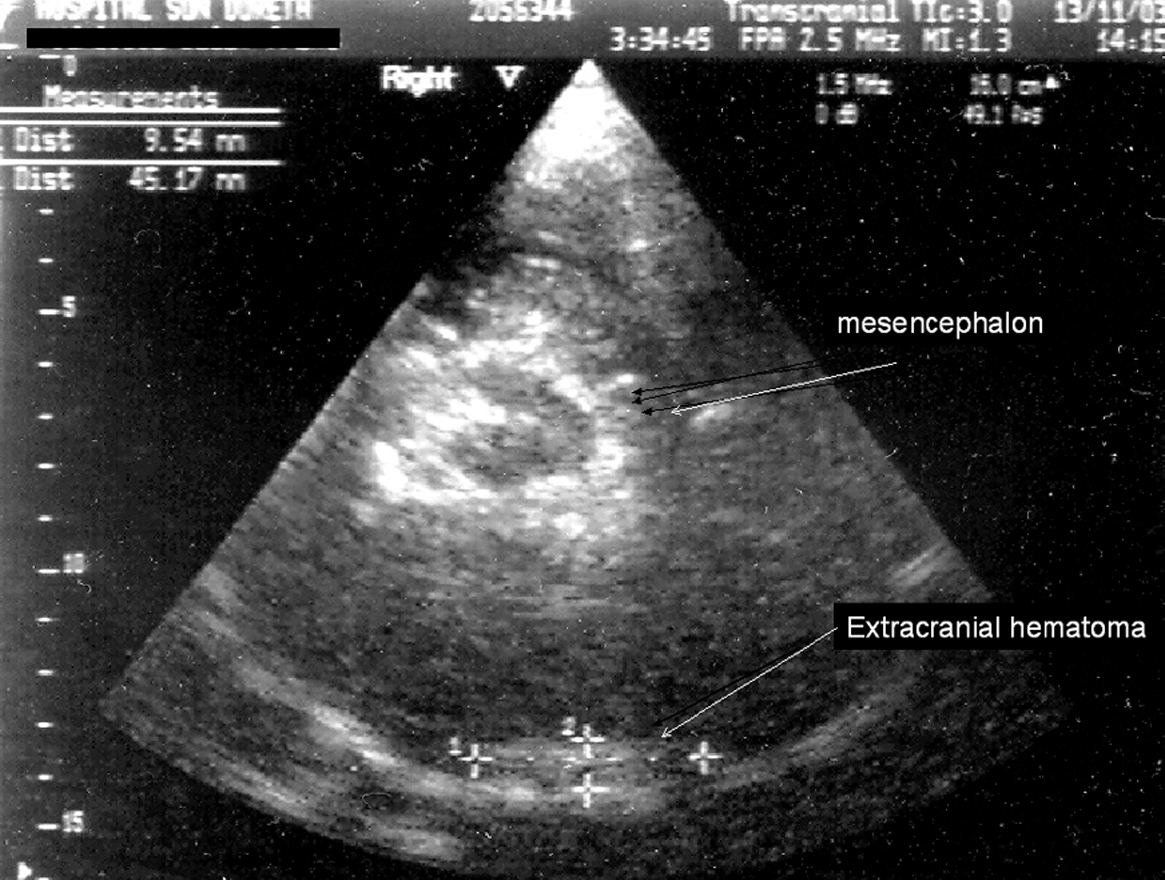

Presentamos el caso de un hombre de 24 años, que sufrió un traumatismo craneoencefálico (TCE), ingresando en una Unidad de Cuidados Intensivos (UCI) con un Glasgow Coma Score de 7 puntos. La tomografía axial computarizada (TAC) craneal mostró un hematoma extraaxial temporal izquierdo no subsidiario de cirugía (fig. 1). A continuación se realizó un dúplex transcraneal con codificación de color (DTCC) que confirmó la presencia de dicho hematoma, mostrando un tamaño de 45 x 9 mm (fig. 2). El hematoma extraaxial se pudo seguir en las siguientes 96 horas mediante DTCC a pie de cama sin apreciarse cambios en su tamaño. Se realizó entonces nueva TAC craneal que corroboró los hallazgos del DTCC. Posteriormente se pudo retirar sedación y extubar, encontrándose el paciente al alta consciente y sin focalidad neurológica.

Figura 2.

El DTCC permite el estudio estructural de los pacientes con TCE a pie de cama, en la Unidad de Neurocríticos, evitando los riesgos de un traslado a planta de radiología.